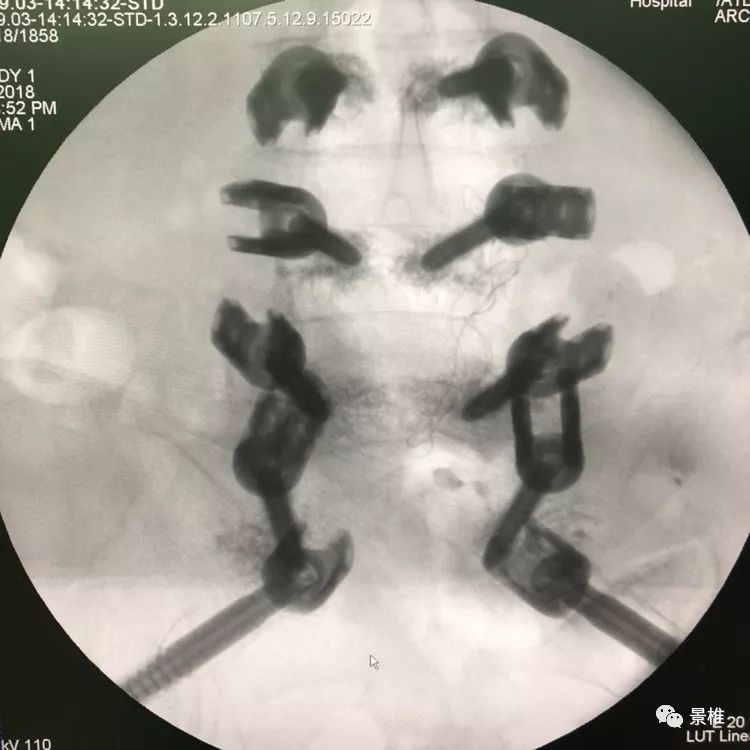

术中C臂头尾侧倾斜20°-30°,左右斜45°透视,确保钉道在泪滴内。注意示意图中球管的位置,不要摆反了。辐射量也小一些 骨科手术C臂透视防护指南